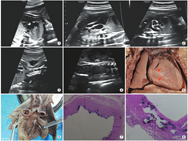

孕妇,26岁,孕1产0,既往体健,孕期无吸烟、饮酒等其他不良因素,配偶体健,非近亲婚配。孕期在烟台山医院定期产检,唐氏筛查低风险,糖耐量实验空腹血糖5.83 mmol/L,餐后1 h血糖10.58 mmol/L,孕24周胎儿系统排畸超声检查示胎儿心脏三尖瓣回声增强,肺动脉瓣环内径2.5 mm,建议随诊复查。孕30周复查胎儿心脏超声示:胎儿主动脉瓣环至升主动脉、肺动脉主干及左右肺动脉近段管壁明显增厚、回声增强,三尖瓣瓣环回声增强,胎儿心脏大小和功能未见明显异常(图1),胎儿降主动脉、腹主动脉及双侧髂动脉、双侧颈动脉均存在管壁明显增厚、回声增强,内径狭窄(图2,图3,图4)。经北京安贞医院母胎医学研究中心远程会诊后,产前超声提示:特发性胎儿动脉钙化症可能性大,并提示预后不良。孕妇及家属决定终止妊娠,并要求进行病理解剖和遗传学检测,以进一步明确病因。于31周行引产手术,分娩一男婴。病理解剖肉眼观示:胎儿主动脉、冠状动脉、肺动脉及腹主动脉、双侧髂动脉及双侧颈动脉管壁增厚、僵硬,管腔狭窄(图5,图6)。组织学检查显示:主动脉和肺动脉管壁内弹性层存在钙化,内膜纤维增生(图7,图8)。遗传学检测提示:胎儿ENPP1基因存在两个复合杂合变异(c.C783G,p.Y26X和c.439delT,p.W147fs),胎儿父母分别携带上述变异中一个,但胎儿父母均无其他临床表型。结合胎儿超声检查、病理学检查以及遗传学检测,本病例诊断为特发性胎儿动脉钙化症。

IIAC患者在早孕期可无明显异常,中晚孕期超声可表现为中-大动脉广泛钙化狭窄、心脏扩大、心功能减低、心包积液、羊水过多等。本例胎儿19周检查未见异常发现,24周超声检查只发现三尖瓣及肺动脉的轻微钙化,31周检查时出现瓣膜及大动脉的广泛钙化。超声和MRI常用于本病的产前检查,但MRI对于钙化的敏感性远不如超声,而CT对钙化灶的发现较敏感,对于出生后的可疑IIAC患者可进行CT检查[3]。